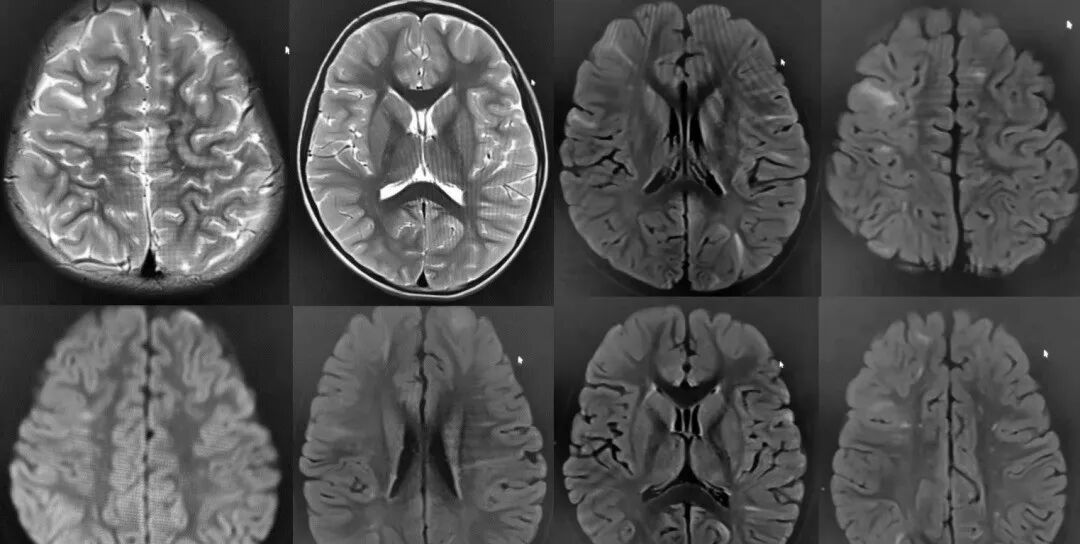

干细胞治疗在神经系统疾病领域的应用越来越受到关注。这类疾病包括帕金森病、阿尔茨海默病和多发性硬化症等,严重影响患者的认知和运动功能。近期,《Stem Cells Translational Medicine》发表的一项研究表明,通过向帕金森病患者的脑内注射间充质干细胞,可以显著改善运动症状,并减少药物使用量。这是因为干细胞能够分化为多巴胺能神经元,补充大脑中缺失的多巴胺神经元,从而缓解症状。

肌萎缩侧索硬化症(ALS)是一种进展性的神经退行性疾病,目前尚无有效治疗方法。然而,干细胞治疗为这一难题提供了新的思路。通过诱导干细胞分化为运动神经元,有望替代受损的运动神经元,从而延缓病情进展。尽管该技术尚处于实验阶段,但已取得了显著成果。此外,研究还表明,干细胞治疗在脑卒中和脊髓损伤等神经系统疾病中也取得了积极效果。这些成功案例为神经系统疾病患者提供了新的治疗选择,展现了干细胞治疗的广阔前景。干细胞治疗心血管疾病是一种创新的医疗手段,对心肌梗死和动脉粥样硬化等心血管疾病表现出显著疗效。研究表明,在心肌梗死模型中,干细胞移植能有效促进心肌细胞再生和修复,从而改善心功能。例如,一项针对心肌梗死的临床试验显示,通过冠状动脉内注射干细胞,可以显著提高患者的心功能和生活质量。此外,干细胞治疗在动脉粥样硬化等疾病中也取得了积极成果。近年来,多项研究表明,干细胞在治疗心脏病方面具有显著效果。通过注射干细胞,可以有效促进心肌细胞的再生,改善心脏功能。一项发表在《欧洲心脏病学杂志》上的研究显示,接受干细胞治疗的患者,其心脏功能和生活质量均得到了显著提升。这些成功案例充分证明了干细胞在心血管疾病治疗中的广阔应用前景,为心血管疾病患者提供了新的治疗选择。呼吸系统疾病,如慢性阻塞性肺疾病(COPD)和肺纤维化,严重影响患者的生活质量。近期研究表明,干细胞移植为这些疾病提供了新的治疗策略。一项关于COPD的研究显示,干细胞注射后显著减轻了肺部炎症,并改善了肺功能。此外,对于肺纤维化,干细胞能够分化为正常肺细胞,替换受损组织。这些成功案例不仅证明了干细胞在治疗呼吸系统疾病中的作用,还展示了其在组织修复和再生方面的巨大潜力。消化系统疾病,如克罗恩病和溃疡性结肠炎,严重影响患者的健康。近期研究表明,干细胞治疗可以有效缓解这些疾病的症状。在一项关于溃疡性结肠炎的研究中,干细胞移植显著降低了肠道炎症,改善了患者的临床症状。此外,干细胞还能够促进肠道黏膜的修复和再生,为溃疡性结肠炎患者带来了新的治疗希望。这些成功案例证明了干细胞治疗在消化系统疾病中的有效性和安全性,为患者提供了新的治疗选择。泌尿系统疾病,如肾炎和肾衰竭,对患者健康造成了严重影响。近期研究表明,干细胞治疗为这些疾病提供了新的解决方案。在一项关于肾炎的研究中,干细胞移植显著减轻了肾脏炎症并恢复了肾功能。对于肾衰竭,干细胞能够分化为肾细胞,替代受损组织,从而改善肾功能。